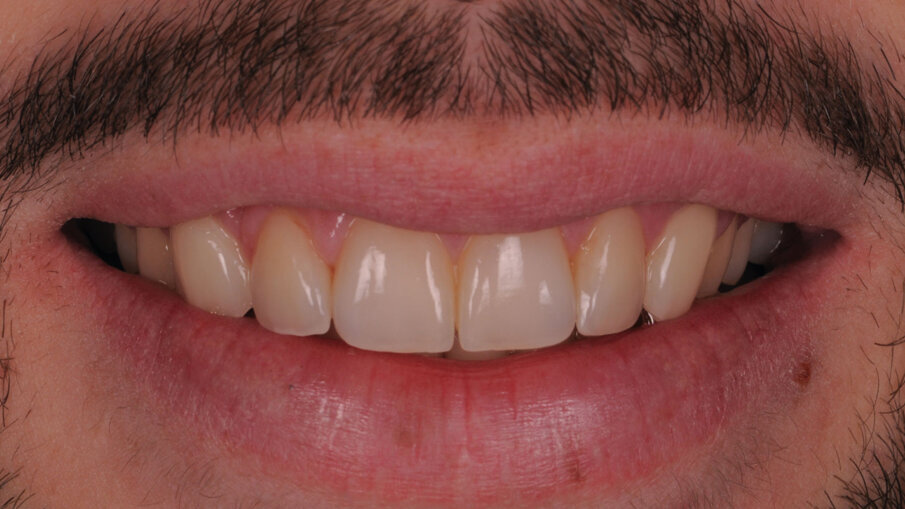

Con questo case report gli autori vogliono trasmettere la loro visione e le loro personali indicazioni cliniche, che portano alla scelta di questo tipo di riabilitazione. Tali riabilitazioni devono essere sì estetiche mimetiche, ma soprattutto devono avere come “goal” il ripristino dei volumi dentali anatomicamente corretti sia nell’aspetto vestibolare che nell’aspetto incisale e occlusale. Il tutto pianificato con un’attenta analisi intra ed extra orale, prestando sempre attenzione alle richieste ed esigenze del paziente, che deve sempre essere al centro del progetto riabilitativo. Non secondaria l’attenzione dedicata alla “componente rosa” della riabilitazione, che deve essere gestita fin dalla fase provvisoria, al fine di avere una giusta “cornice” per i nostri manufatti che, sottolineiamo, sono pertinenza delle mani sapienti dei nostri odontotecnici (Figg. 12a, 12b).